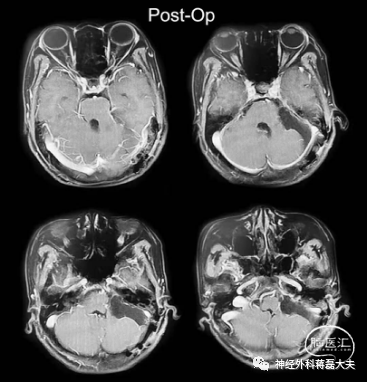

经过充分术前准备,在麻醉医师密切配合下,历时3.5个小时,显微镜下顺利肿瘤全切,手术丝毫未损伤脑干旁血管及细小穿支血管及附近颅神经,术中出血仅50ml,手术过程未输血,肿瘤切除后整个脑干及表面血管、神经完美呈现在显微镜下。

(术后)

术后患者恢复理想,饮水呛咳、声音嘶哑症状好转,颅神经功能逐步恢复,很快可行走自如,顺利出院。